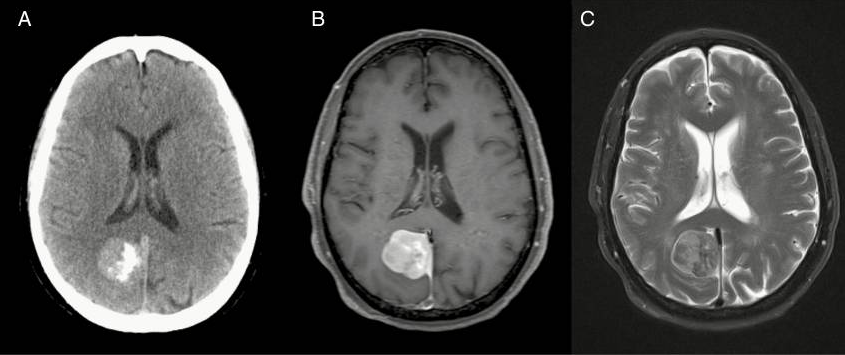

腦膜瘤的影像學(xué)診斷通常依賴于計(jì)算機(jī)斷層掃描和核磁共振成像的評(píng)估。然而,將殘留或復(fù)發(fā)的腫瘤與手術(shù)后或放射治療的變化區(qū)分開來有時(shí)可能具有挑戰(zhàn)性。在這些情況下,現(xiàn)代成像技術(shù)已經(jīng)利用了腦膜瘤生物學(xué)的特定屬性:例如,核閃爍掃描或正電子發(fā)射斷層掃描(正電子發(fā)射斷層掃描)可以檢測(cè)放射性標(biāo)記的奧曲肽(一種生長(zhǎng)抑素激動(dòng)劑)及其與腫瘤特異性生長(zhǎng)抑素受體的結(jié)合(如SSTRⅱ)。

戈弗雷·豪恩菲爾德爵士在1973年引入了計(jì)算機(jī)斷層掃描,保羅·勞特布爾在1973年引入了磁共振成像,這開啟了影像學(xué)在腦膜瘤診斷和治療中的重要作用。這些強(qiáng)有力的方法,加上靜脈注射造影劑,闡明了腦膜瘤的軸外解剖起源,它們的生長(zhǎng)模式,硬腦膜的擴(kuò)散經(jīng)常遠(yuǎn)遠(yuǎn)超出腫瘤體積的限制,鄰近骨的可變受累,溶解或骨質(zhì)增生的變化,以及神經(jīng)血管結(jié)構(gòu)的典型受累和偏斜。通過CT和MRI對(duì)腦膜瘤外觀和鄰近組織的獨(dú)特分辨率刺激了術(shù)前計(jì)劃和手術(shù)技術(shù)的平行發(fā)展,增強(qiáng)了對(duì)手術(shù)風(fēng)險(xiǎn)的認(rèn)識(shí),并允許從多個(gè)間隔區(qū)更明確地切除腦膜瘤。此外,重要的動(dòng)脈和靜脈關(guān)系現(xiàn)在可以用計(jì)算機(jī)斷層掃描或磁共振血管造影術(shù)進(jìn)行更詳細(xì)的研究。